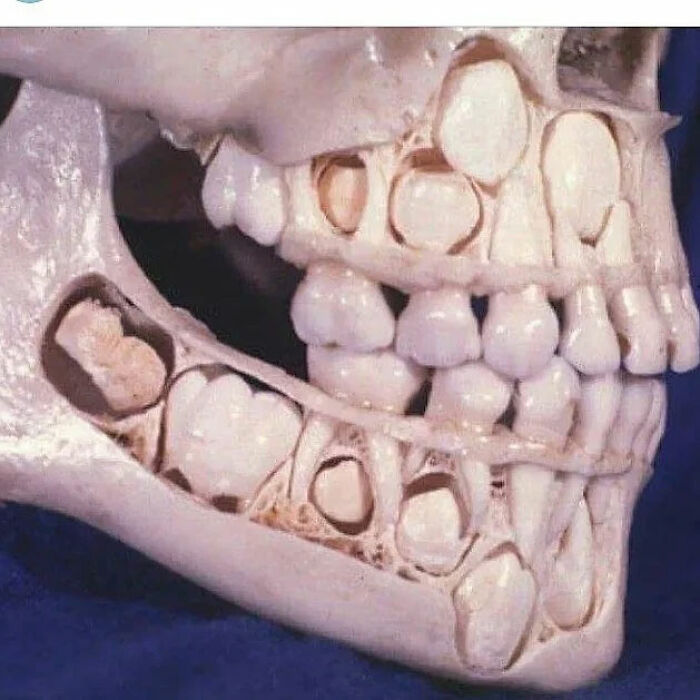

#25 Child Mouth Before Loosing Their Teeth

Image source: medical_pedia